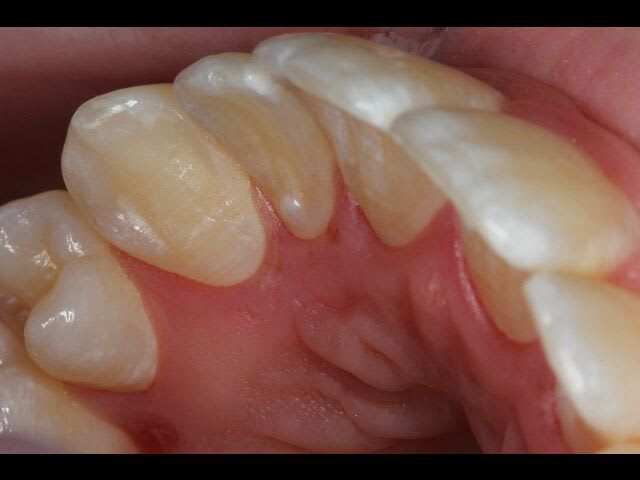

Patient 17 ans. Traitement ortho terminé. Il a présenté il y a environ 4 mois une ulcération symétrique en palatin de 15 et 25.Ces ulcérations sont asymptomatiques. Le patient ne s'en plaint pas. Aucune gêne ni douleurs.Cicatrisent naturellement et réapparaissent.

De retour ce matin, adressé par l'ortho car début d’ulcération nouvelle, tjrs symétrique en palatin de 12-13 et 21-23.

Le plus inquiétant c'est la récession gingivale. Pas de mobilité pour le moment. Hygiène correcte.